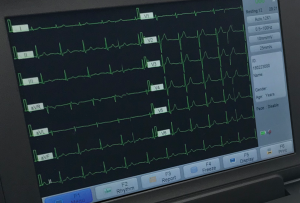

Dependable EKG Monitors for Your Practice Electrocardiogram monitors, or EKG patient monitors, have several purposes in healthcare

An Electrocardiograph Machine with Innovative Interpretation Software An electrocardiograph machine tracks the electrical activity of a patient’s